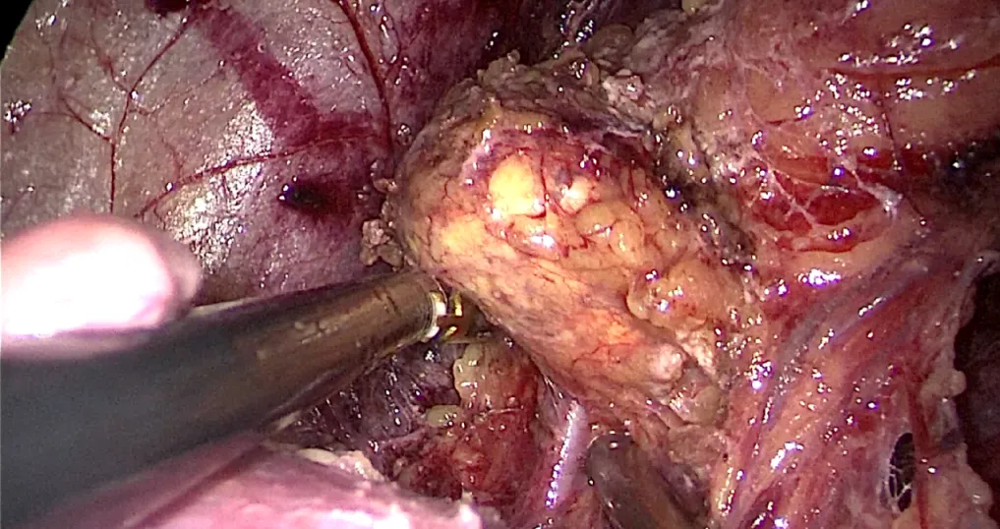

一、泌尿外科:精准微创,攻克腹膜后肿瘤

针对肾上腺肿瘤等腹膜后复杂占位,泌尿外科团队熟练掌握腹腔镜微创技术。近期,一例因体检发现肾上腺占位的患者,经影像评估与内分泌检查,高度怀疑嗜铬细胞瘤。团队充分进行术前扩容降压准备,成功实施“腹腔镜下左侧肾上腺全切术”。术后病理确诊为嗜铬细胞瘤(恶性潜能)。此类手术风险高、操作精细,我院团队凭借娴熟技术,实现了肿瘤完整切除,患者恢复良好,彰显了在复杂内分泌肿瘤微创手术领域的专业能力。